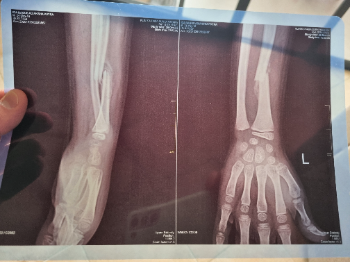

26.12.2025: Der 7 jährige Aksha hat sich vor 2 Wochen den Arm gebrochen (siehe Röntgenbild). Leider können sich seine Eltern noch nicht einmal die einfachste Versorgung leisten. Das Röntgenbild wurde heute erst gemacht, 26.12. 2025, da ich dafür bezhalt habe. Der kleine Junge muss später seine Eltern mitversorgen können und hierzu braucht er zwei gesunde Arme. Eine OP um den Bruch zu korrigieren ist unumgänglich. Eine deutsche Ärztin konnte mir das nach Begutachtung des Röntgenbildes bestätigen. Ich bin noch vor Ort und möchte morgen (27.12.26) mit dem Jungen und seinen Eltern ins Krankenhaus. Für OP und Nachsorge vermute ich, sind 3.000 Euro nötig. Ich selbst starte mit 500 Euro. Bitte helft mit, jeder kleine Euro zählt.